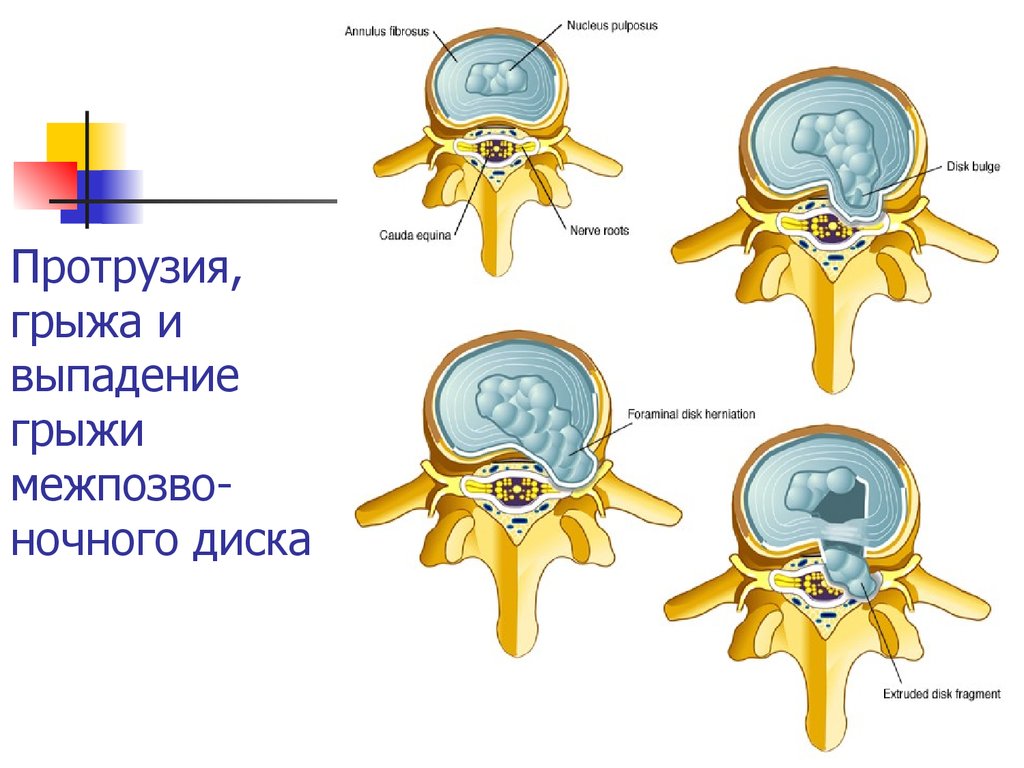

КТ-протрузии дисков: Визуализация и классификация